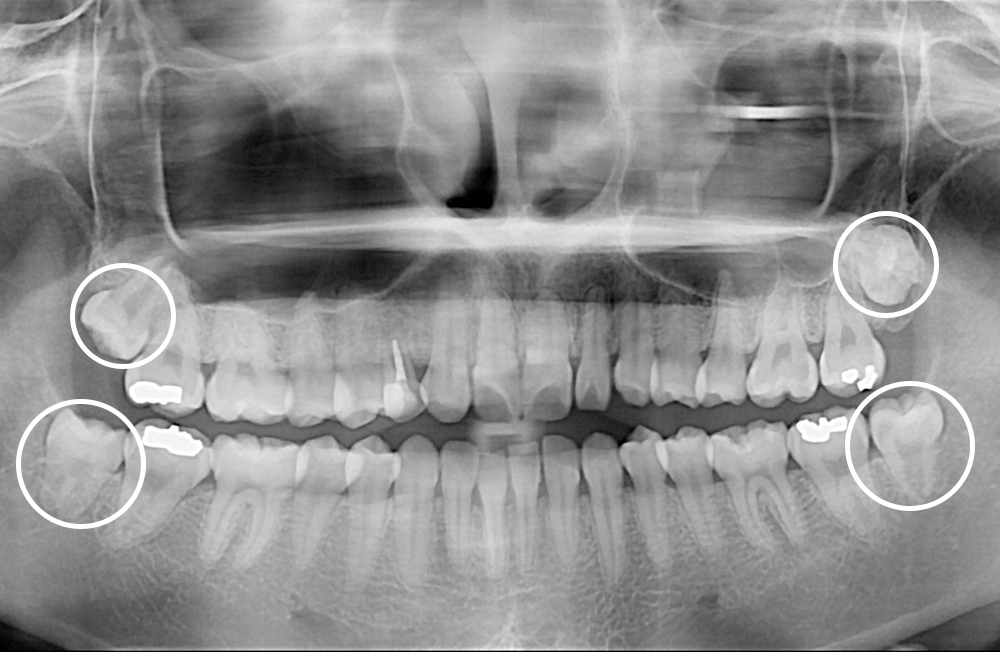

[사랑니] 매복 사랑니 발치

치료전 : 2020-06-16

치료후 : 2020-07-18

세종치과는 구강악안면외과학 박사이신 원장님이 발치하는 치과입니다.